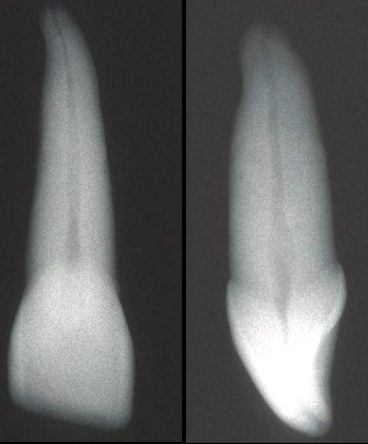

What is the canal shape of a maxillary central incisor?

Usually round

What is the canal shape of a maxillary lateral incisor?

Usually oval / round

When creating your access in maxillary central incisors, what should you observe in your radiograph?

Anatomy, shape, and location of canal